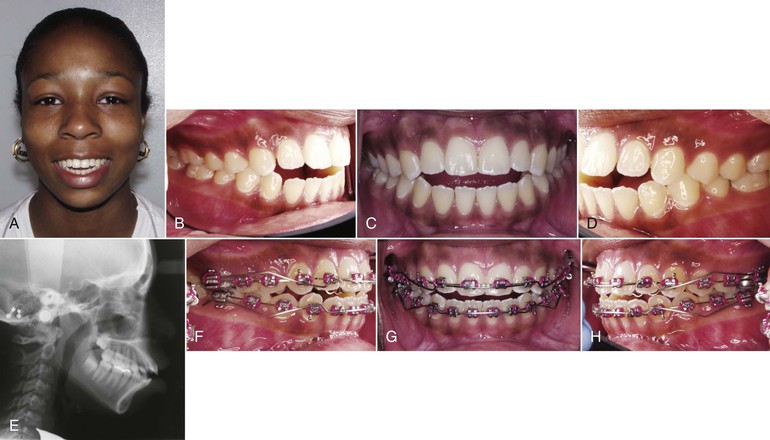

Management of adult patients with vertical maxillary excess and excessive vertical dimension has been addressed primarily through orthognathic surgery.98 Surgical procedures to address long face patients have been associated with acceptable treatment outcomes and long-term stability.99,100 However, the introduction of skeletal anchorage devices has been a major shift in orthodontics, enabling predictable, effective, and efficient tooth movements with direct occlusal and skeletal benefit to long face patients.101,102 The molars can be intruded directly from TADs to correct the vertical dimension without the need for compliance by the patient.103–105

A major advantage of molar intrusion with TADs is the favorable skeletal changes that enhance a patient's dentofacial esthetics (Fig. 9-20). With conventional orthodontics in patients with anterior open bite, closure of the overbite is achieved mainly through dentoalveolar changes; however, the skeletofacial complex may worsen because of extrusive mechanics. On the other hand, TADs target the intrusion of the posterior segment, which is often the cause of the increased vertical dimension.

Figure 9-20 Adult patient with a moderate skeletal anterior open bite treated with temporary anchorage devices (TADs). A–C, Extraoral views show increased lower facial height and adequate incisor display at smile. D–F, Anterior open bite with occlusal planes that diverge anteriorly from the second molars. G–I, Four TADs (two in the infrazygomatic crest and two in the external oblique ridge) were placed to assist in the intrusion of the first and second molars. J–L, Final extraoral views showing good esthetic result, including maintenance of the incisor display upon smiling. M-O, Final intraoral views depicting anterior open-bite closure. Note that the mandibular right second molar was intentionally overintruded to leave adequate space for a restoration since this tooth had significant occlusal wear through dentin with the pre-treatment occlusion. P-R, General and regional superimpositions show molar intrusion and vertical maxillary incisor control.